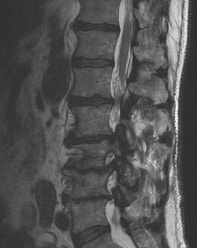

In some people this degenerative process is not associated with pain, while in others degenerative disc disease can cause neck and back pain, stiffness, and soreness. Degenerative discs can rupture, leading to arm or leg pain if the disc pinches nerves. The process of degeneration causes discs to gradually lose height, form spurs, and cause narrowing around the nerves, which can also lead to arm and leg pain